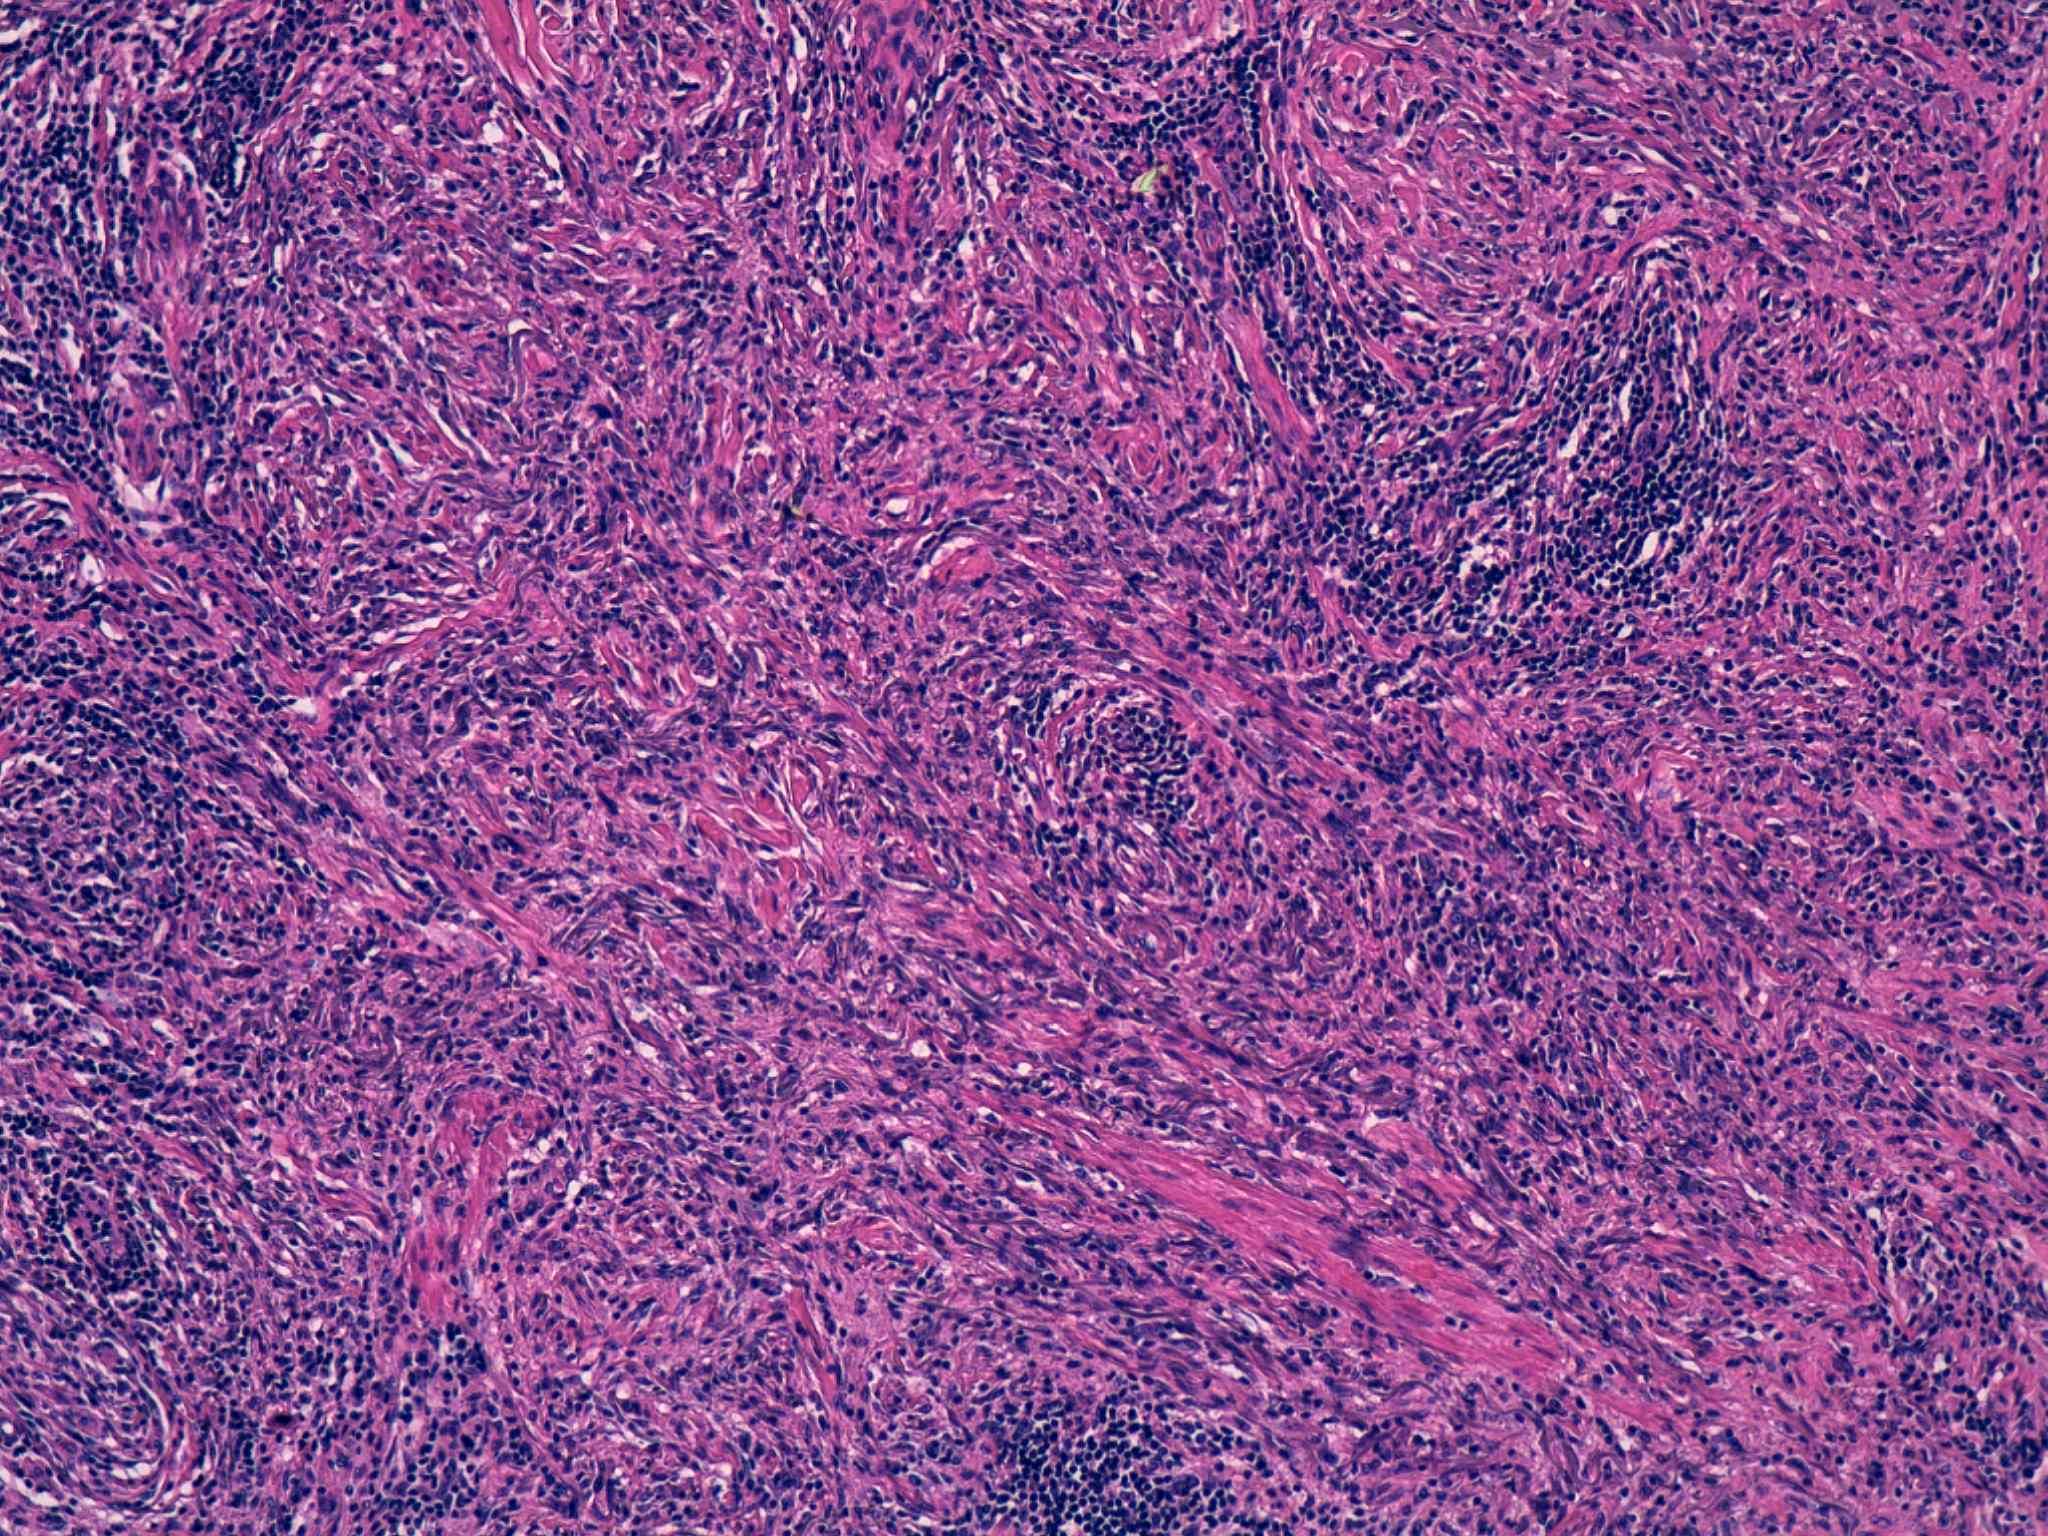

14 -- image_2011y10m04d_17h50m22s.jpg